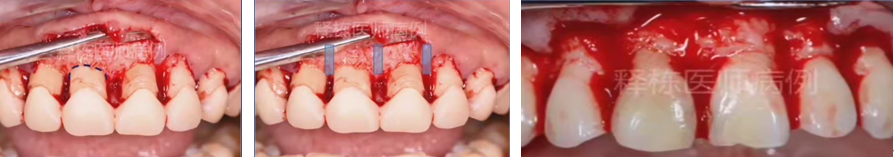

沟内切口,不伤牙龈,保留龈乳头,缝合前修剪内侧牙龈。

翻瓣至膜龈结合,根向复位(勿做垂直切口——骨吸收,龈退缩。腭侧可适当去除一点牙龈),保留角化龈。

3、用小/中球钻,后用刮治器去除近牙面的牙槽骨,形成一个缓坡。3.5-4mm。

4、刮治器修整后(去除牙周膜等),去除肉芽组织,复位牙龈,看牙龈有多,沿内侧修剪多余牙龈。(告知患者牙龈消肿后有间隙,需牙间刷清洁)

局麻下翻瓣

术中

翻瓣后清除炎性组织

颈缘骨修整

软组织修复整

间断缝合